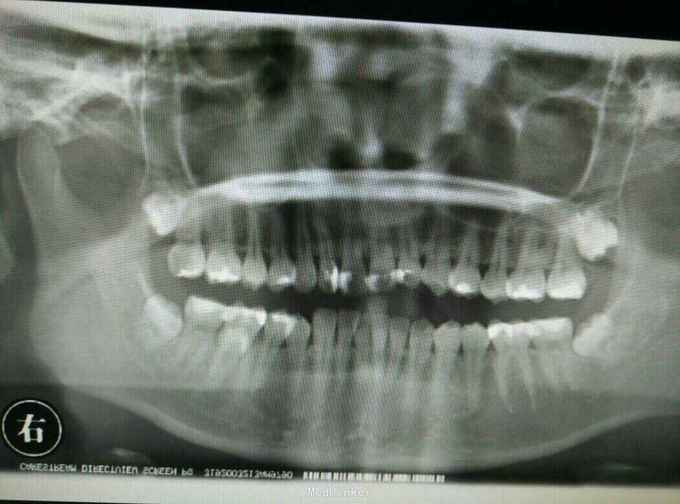

体查见46舌侧一骨性隆起,扪诊质硬。粘膜表面稍白。余检查无特殊。予患者口腔全景片检查,排除颌骨病变。提示46根部高密度影,根交低密度影。于是再次行根交片检查,结果提示:46根部多生牙。